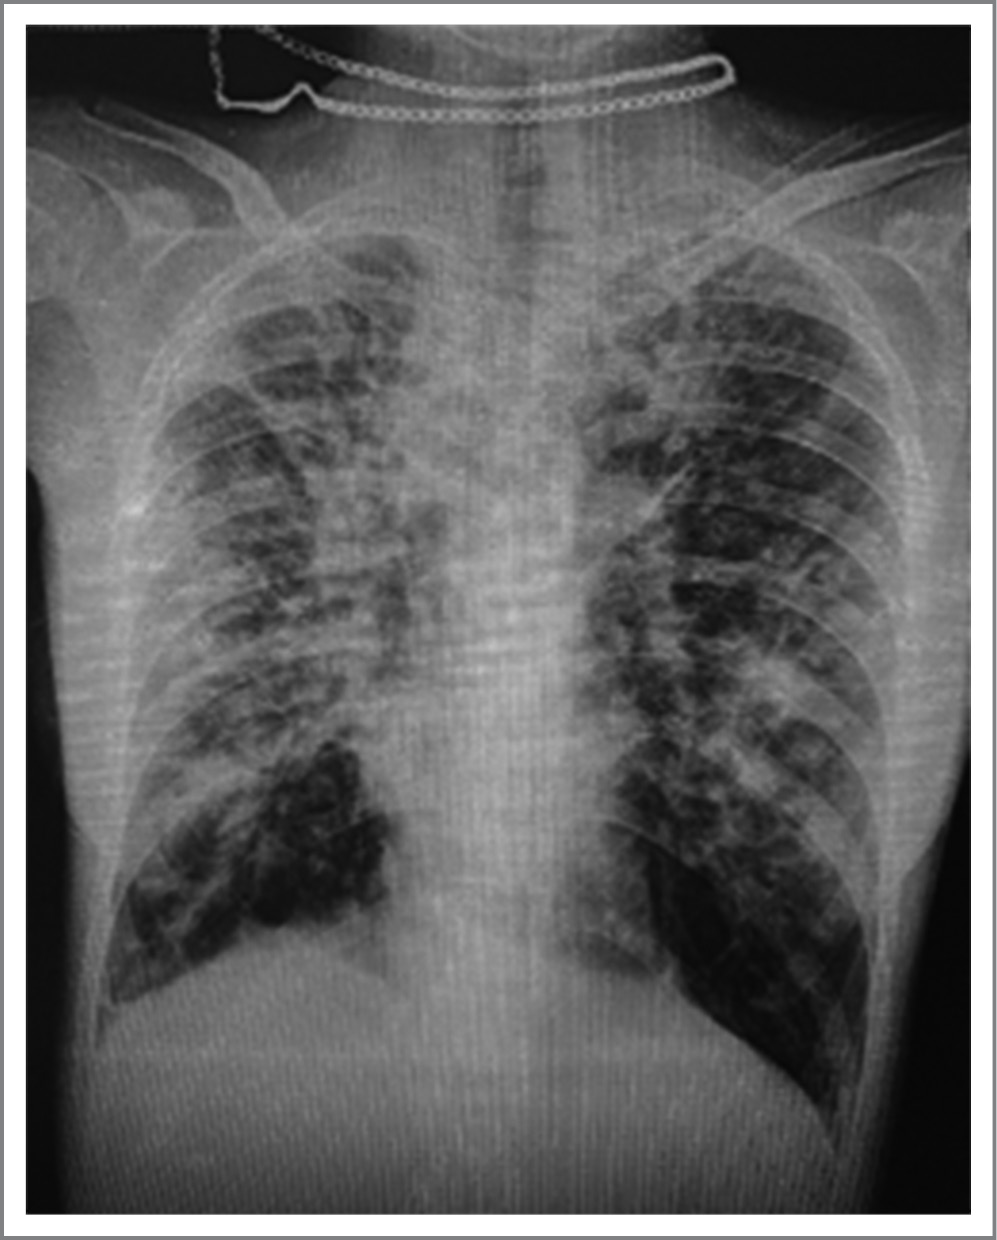

КТ ОГК с болюсным усилением – полученные данные могут соответствовать кистозной трансформации легких, множественным бронхо- и бронхиолоэктазам с двух сторон, участкам перибронхиальной инфильтрации воспалительного генеза, мозаичной легочной плотности, правостороннему малому плевральному выпоту, внутригрудной лимфаденопатии, небольшой передней клиновидной деформации тела LI (рис. 3). Описанные изменения обусловлены синдромом Уильямса–Кэмпбелла. Данных за тромбоэмболию легочной артерии нет.

Рис. 3. Кистозная трансформация легких, множественные бронхо- и бронхиолоэктазы.

Fig. 3. Cystic transformation of the lungs, multiple broncho- and bronchiolectasis.